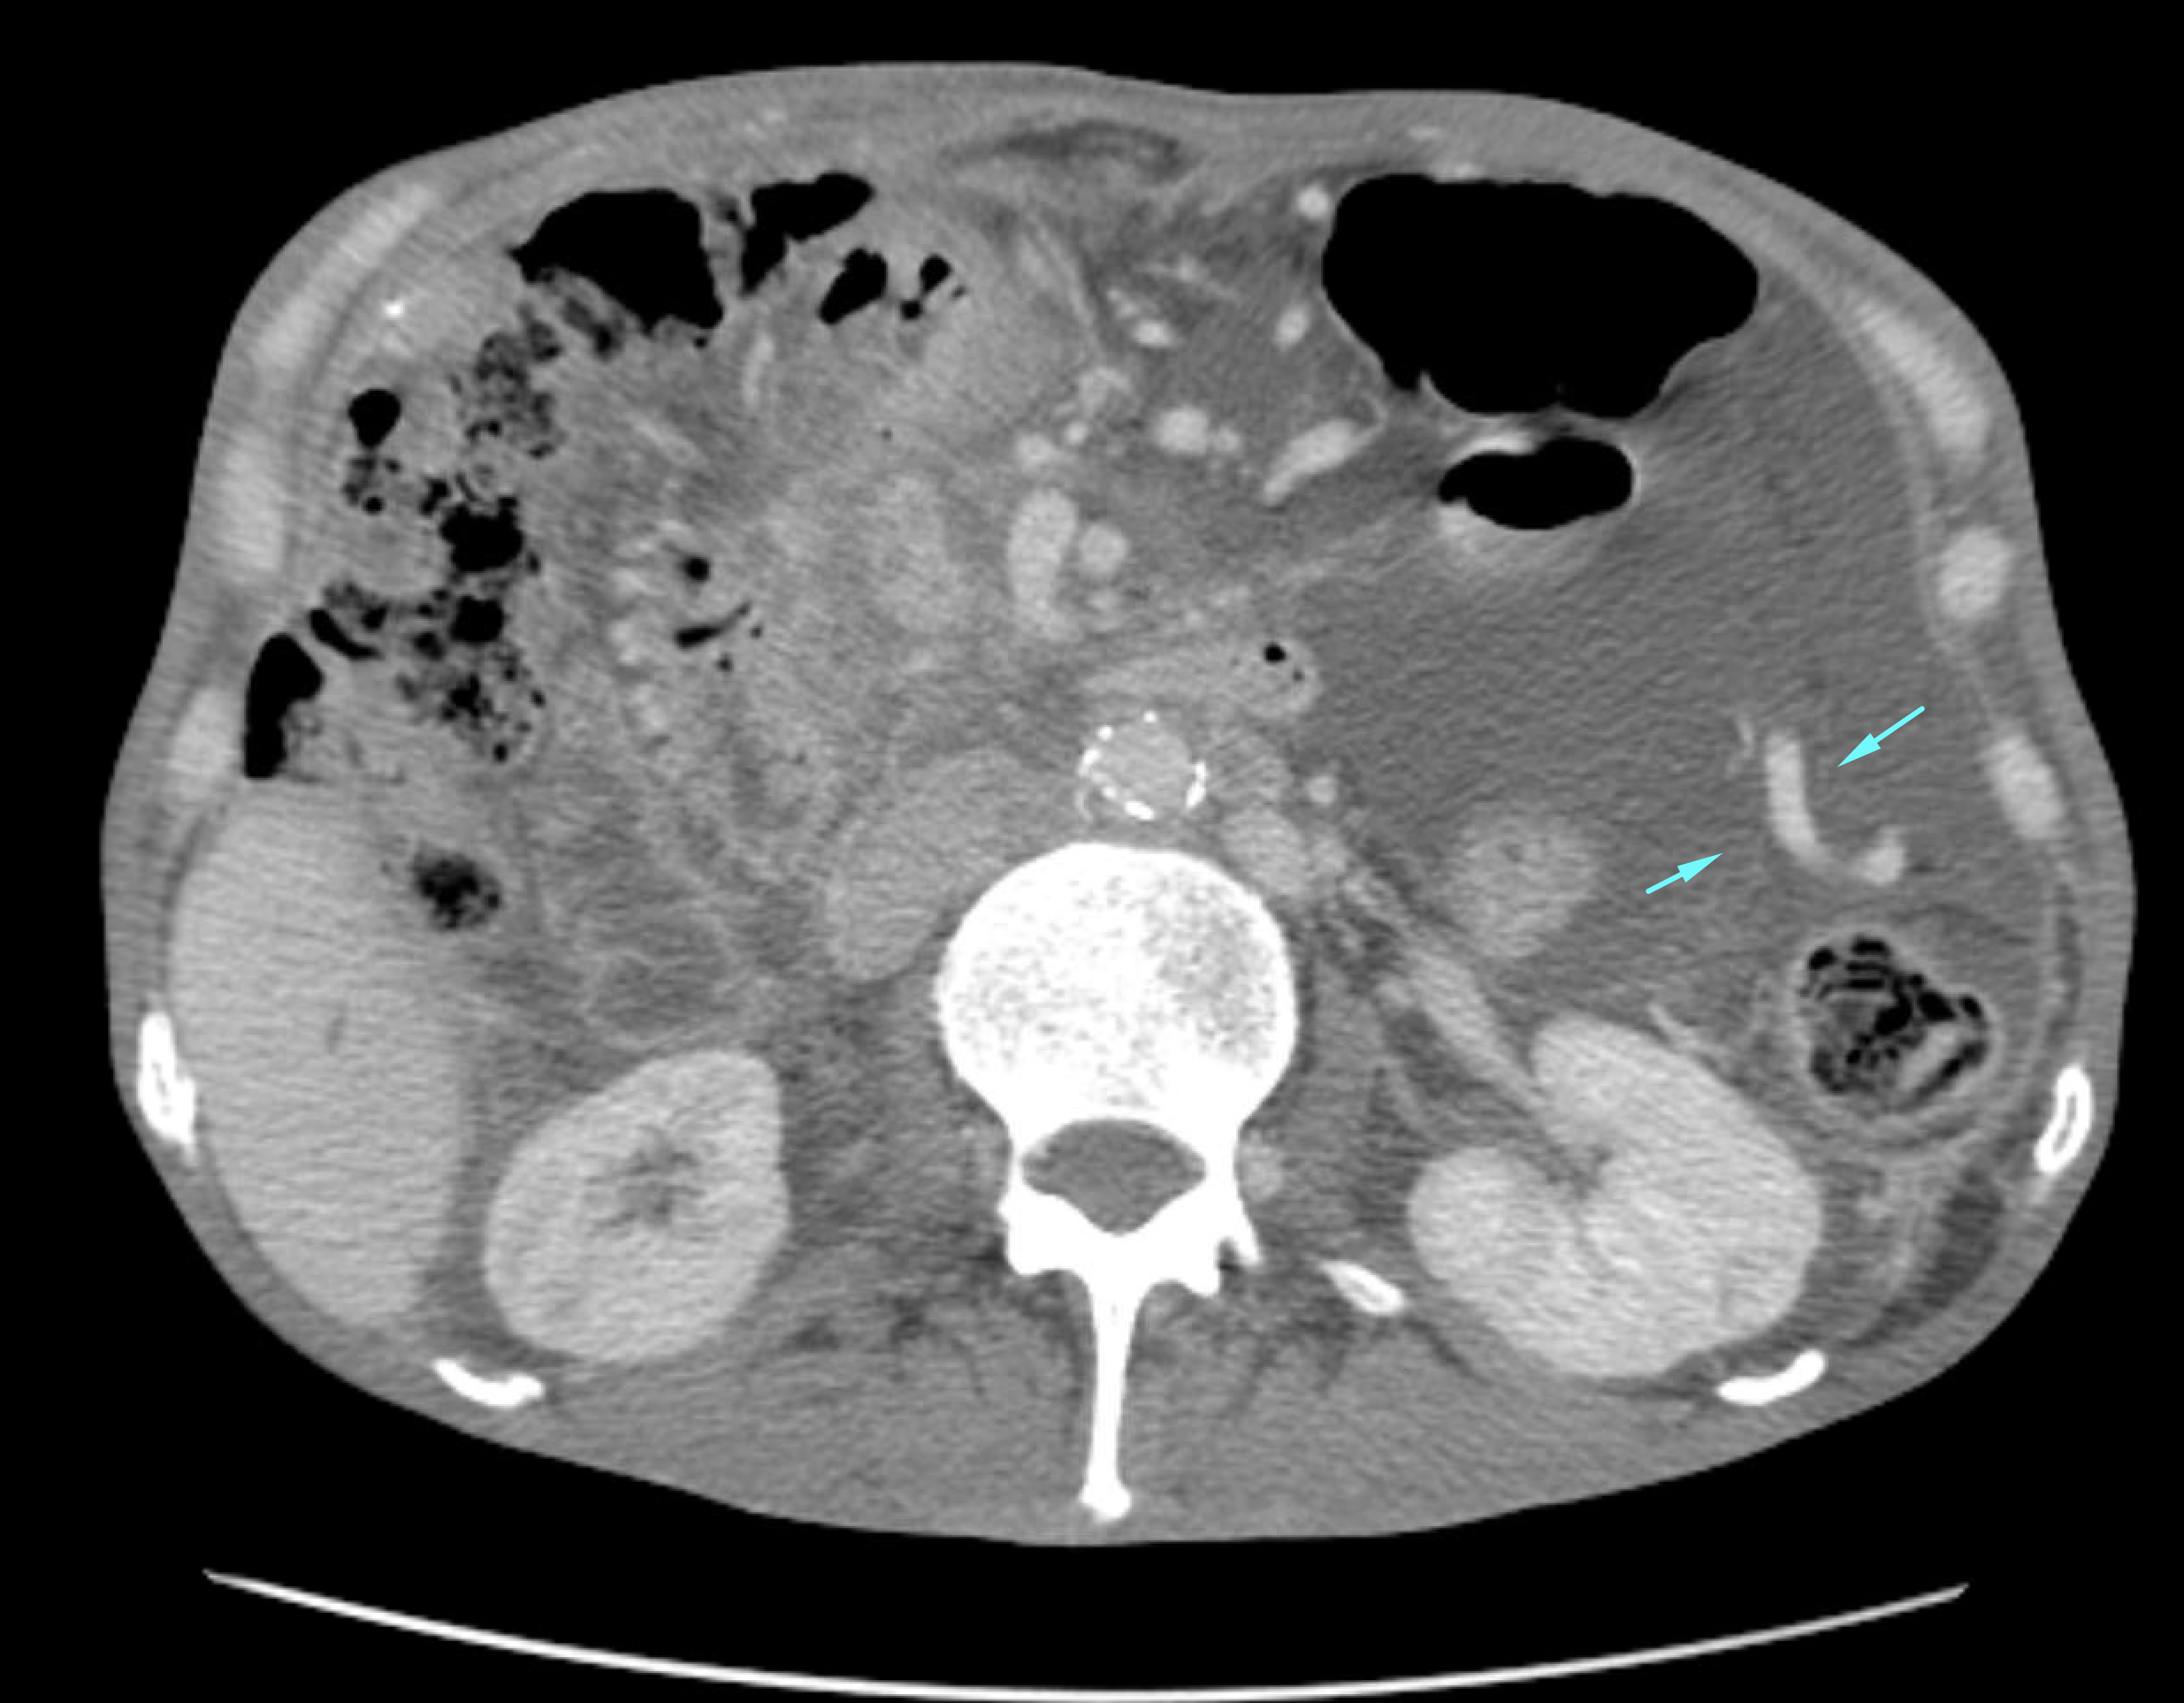

Age: 69

Sex: Male

Indication: GI bleeding

Radiotracer: Tc99m labeled RBCs

Sample ReportNo evidence of active GI bleeding during the course of this study.